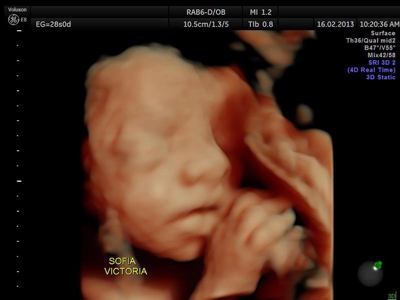

Si bien la Ecografía 4D HD/5D puede realizarse en cualquier etapa del embarazo, recomendamos realizarla entre las semanas 24 a 32 de gestación ya que se pueden observar rasgos bien definidos en el bebe.

Fotografías de ecografías 4D HD/5D

Haga click sobre las imágenes para ampliar